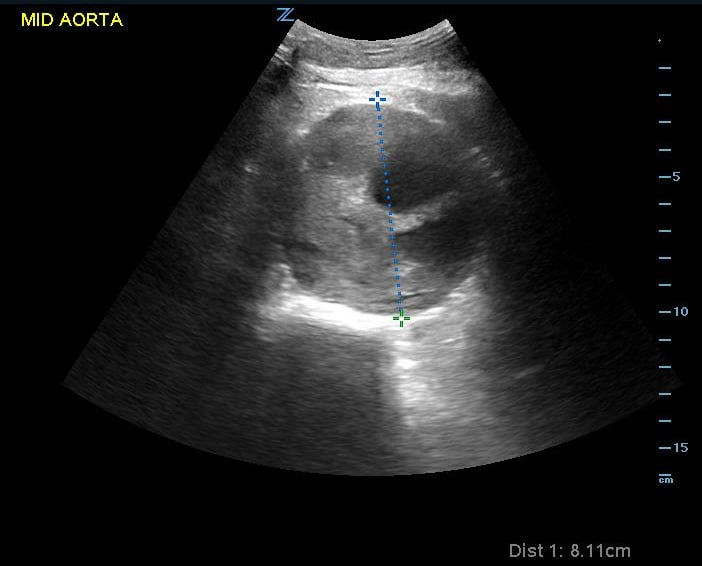

Ultrasound is a valuable modality for determining presence of AAA. This is defined as an aortic diameter > 3cm. Though determination of ruptured AAA is difficult by ultrasound alone, RUSH and similar protocols rely on making a presumptive diagnosis of ruptured AAA as a cause of shock when the aortic diameter measures larger than 5cm while a normal aortic exam would make this diagnosis very unlikely. When performed as part of a rapid evaluation in a hypotensive patient, the most efficient location to visualize is the infrarenal aorta. (Video 16) (Figure 12)

Figure 12. Image of abdominal aortic aneurysm measurement. Note luminal thrombus present. Measurement should thus be taken from outside wall to outside wall